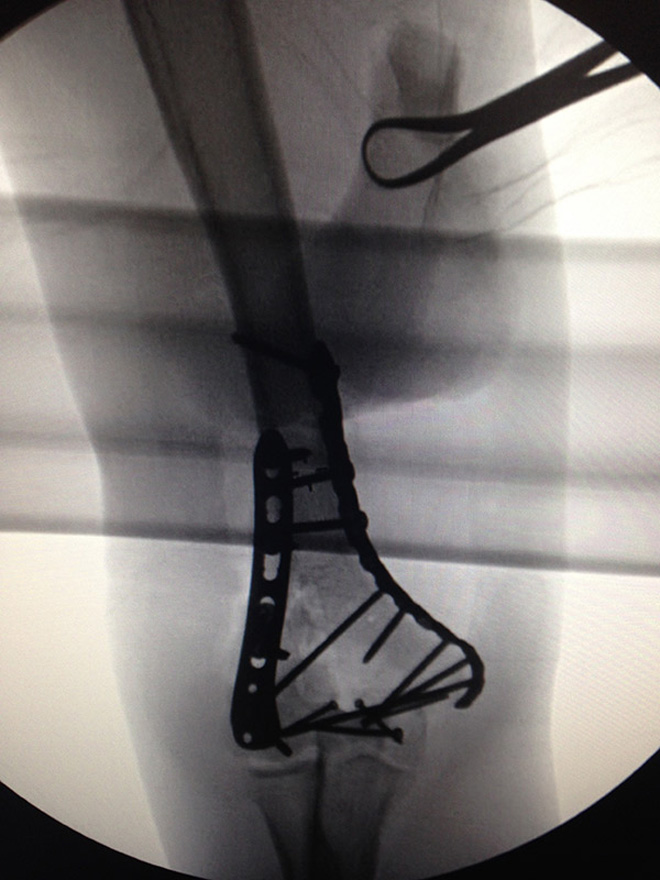

「個人的には、グリーンのアイリッシュ・ファルコンや(RED)グレッチのフレットをいじくれなくなったとしたら、すごく寂しくなるだろう」「でも、エッジだったりジミー・ペイジだったり君らが知るギタリストで、いまの僕のようにチタンの肘を持つ奴がいるかい?」

そして、Xのところで、その“チタン肘”のX線写真を公開した。